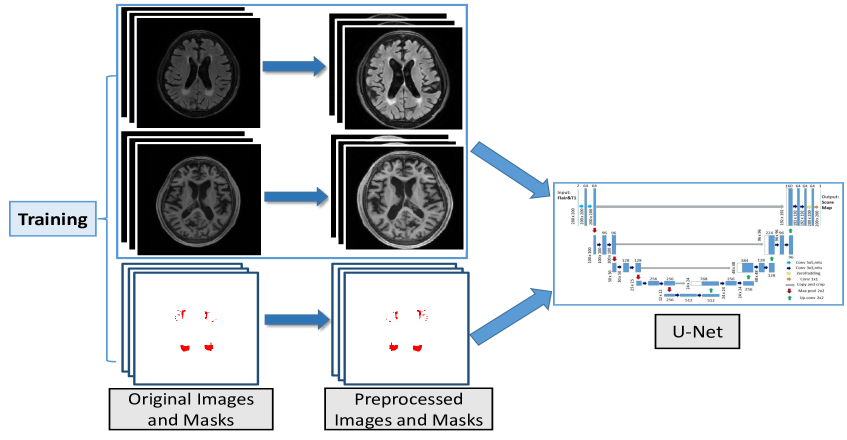

3.1 Further Preprocessing

A further preprocessing on top of the basic preprocessing steps pursued by the organizers (Section 2.2) plays an important role in our overall framework. We aim at employing a simple and effective preprocessing step on both training and held-out testing set. It is motivated by three objectives: 1) to guarantee a uniform size of all data for deep convolutional networks in the training and test stage, 2) to normalize voxel intensity to reduce variation across subjects. and 3) to equip the CAD system with desired invariance and robustness. We enforce these desired data properties by implementing further steps in the training of our algorithm: 1) cropping or padding each axial slice to a uniform size, 2) Gaussian normalization on the brain voxel intensity, and 3) data augmentation on the processed images. Most of these steps are performed for both FLAIR and T1 modalities and for both the training and test stages. Data augmentation was performed only during the training stage.

Firstly, all the axial slices were automatically cropped or padded to , in order to guarantee a uniform size for input to the deep-learning model. Secondly, Gaussian normalization was employed to normalize the intensity distributions for each 3D scan. This includes three steps. Firstly, a threshold was empirically set to obtain an initial binary brain mask. Secondly, for each axial slice of the obtained binary masks, the largest connected component was selected. Thirdly, the holes inside the connected component was filled using morphology operations. Thus a final brain mask was obtained for each slice. For each 3D scan, Gaussian normalization was then employed to rescale the voxel intensities within each individual’s brain mask.

3.1.1 Data augmentation

Figure 3 shows an example of the resulting slices after applying the transformations. After data augmentation, we obtain a dataset ten times larger than the original one.

3.2 Fully Convolutional Network

Convolutional neural network has proven to be an effective computational model for automatically extracting image features. Recently the fully convolutional networks (FCN) (Long et al., 2015) and their its extensions (Milletari et al., 2016) have been used for medical images segmentation. We build a variant of FCN architecture based on U-Net (Ronneberger et al., 2015), which takes as input the axial slices of two modalities from the brain MR scans during both training and testing. Our network is shown in Figure 4. For each patient, the FLAIR and T1 modalities are fed into the U-Net jointly as a two-channel input. It consists of a down-convolutional part that shrinks the spatial dimensions (left side), and up-convolutional part that expands the score maps (right side). The skip connections between down-convolutional and up-convolutional were employed.

As shown in Figure 5, U-Net models with same architecture are trained with random parameter initialization and shuffled data in the batch learning. For each of the U-Net models, when given a test image, a probability segmentation map will be generated by that model. Then the resulting maps will be averaged. Finally an empirically-picked threshold will be used to transform the scores map into a binary segmentation map.